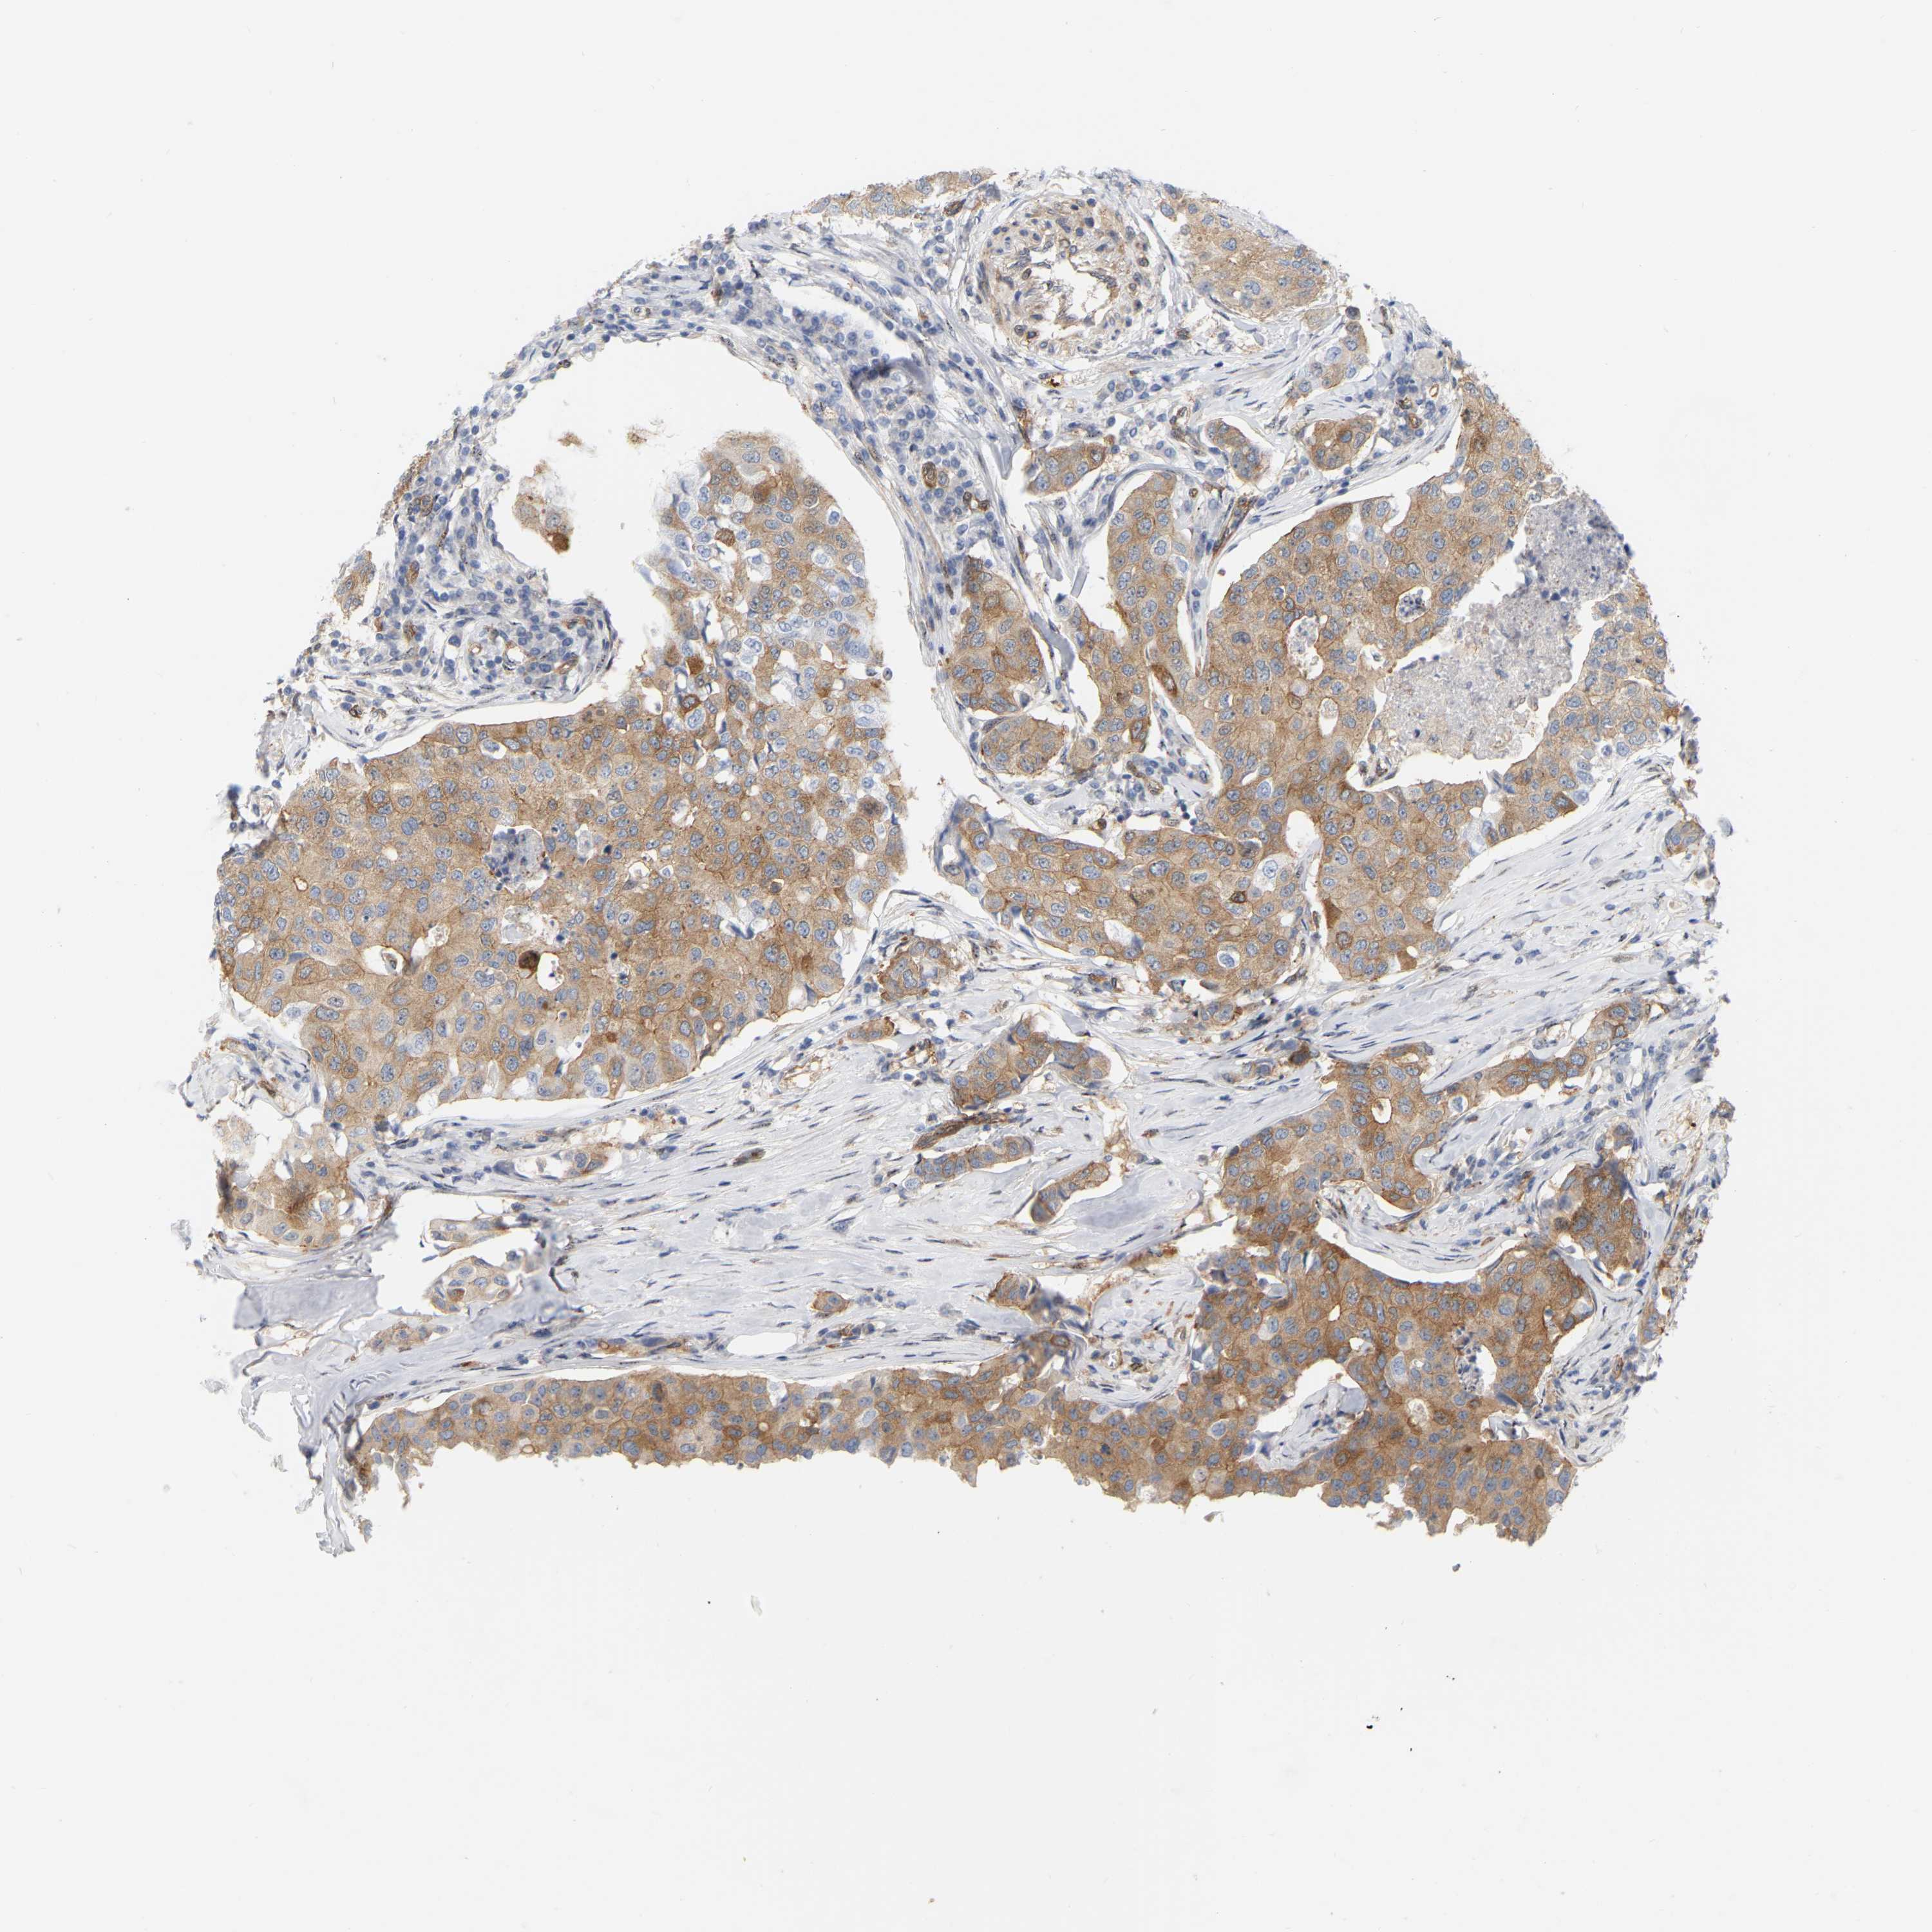

CANCER BREAST CANCER Show tissue menu

BRCA TCGA BRCA VALIDATION PROTEIN EXPRESSION

Breast cancer

Human cancer